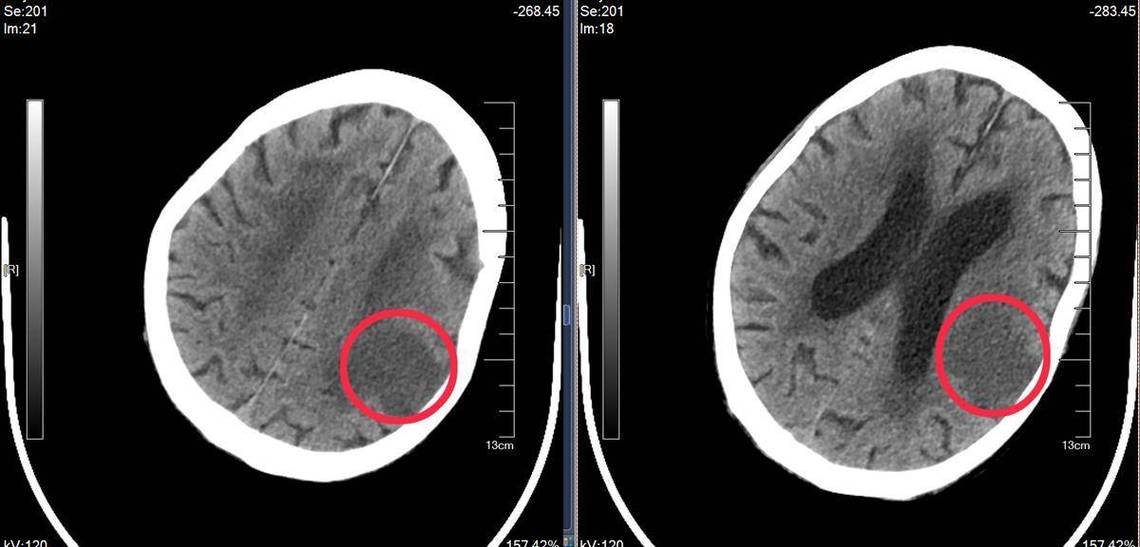

这个诊断描述的是梗塞灶的大小和位置。

“脑梗”:全称是“脑梗死”,就是我们常说的“中风”的一种,它指的是大脑的某一部分因为血液供应被中断,导致脑组织缺血、缺氧,最终坏死,就像一块田地因为缺水而庄稼枯死一样。

“毛细血管”:这是关键点,它告诉我们,这次堵塞发生的血管非常细小。

- 毛细血管是大脑最微小、最末端的血管,负责给神经细胞输送氧气和营养。

- 堵塞发生在毛细血管,意味着梗塞灶非常小,通常只有几毫米,甚至更小。

这种梗塞因为病灶小,通常被称为“静息性脑梗”或“无症状性脑梗”,因为它很多时候不引起明显的、严重的症状,或者症状非常轻微、短暂,容易被忽略。